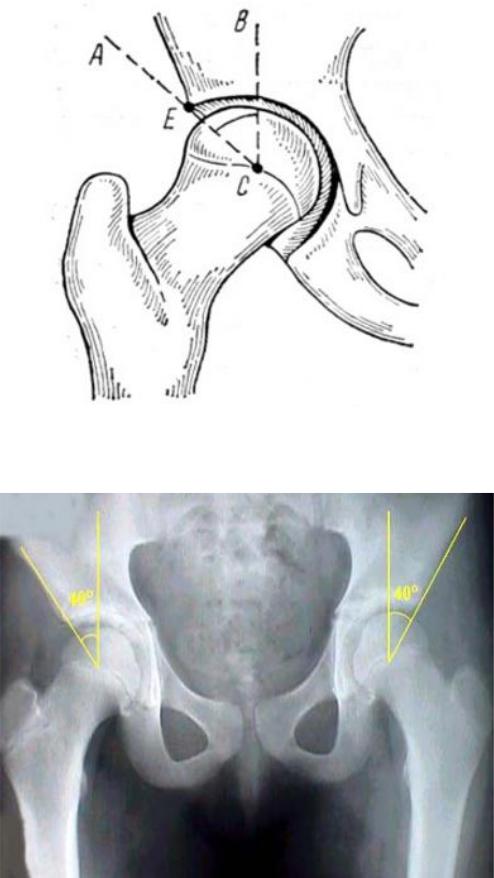

Рис. 77. Макропрепарат тазобедренного сустава новорожденного (А – угол вертикального наклона вертлужной впадины; B – шеечнодиафизарный угол; C – угол вертикального соответствия)

Проксимальный конец бедра характеризуют следующие показатели (Рис.

78):